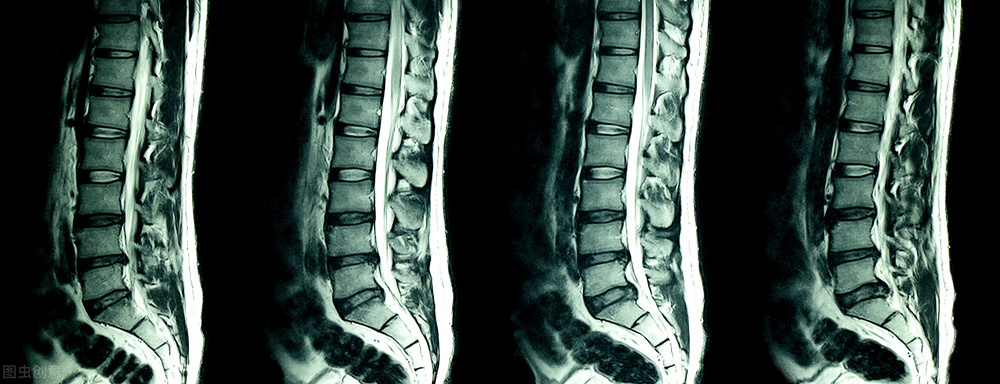

症状:腰椎间盘L3-4突出,L4-5脱出,L5-S1膨出,硬膜及神经受压

无奈,这次去了上海六院拍片看了下,拿到CT报告后显示结果非常严重:腰椎间盘L3-4突出,L4-5脱出,L5-S1膨出,硬膜及神经受压,骨性椎管无狭窄……